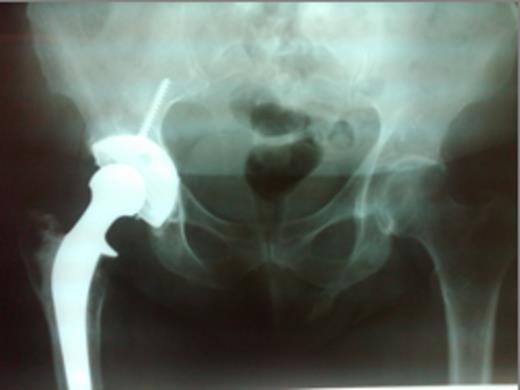

Review of her radiographs demonstrated a well-positioned right total hip arthroplasty without any evidence of loosening or wear. Her left hip was unremarkable. However, there was an osseous growth projecting from the inferior aspect of left ischium toward the perineal region. Additional imaging with computed tomography (CT) and non contrast magnetic resonance (MR) were used to further define the lesion.

Representative images, including: a plain radiograph (Figure 1), 3D reconstructed computed tomography (Figue 2) and T1 coronal magnetic resonance imaging (Figure 3) indicated a bony excrescence from the inferior aspect of the left ischium measuring 1.7 x 1.1 cm. MR without gadolinium did not show any surrounding inflammatory changes. No aggressive features were seen on the studies. Review of a previous CT scan from 2 years prior to the most recent study, demonstrated a stable lesion.

Plain X-ray: AP pelvis demonstrating pelvic digit arising from the left ischium